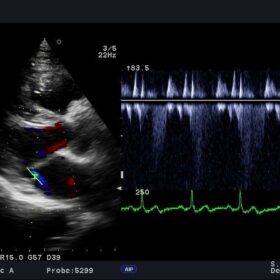

The B-mode brightness is adjustable with a single keystroke as is automatic optimization of the spectral waveform. Based on the users’ previously demonstrated preferences. The Auto Angle Correct function allows easy adjustments of beam-to-flow angle in the PW Doppler mode to significantly improve measurement accuracy.

The Free Angular M-mode (FAM*) can be implemented in real time or reconstructed from the cine memory. Orientation at arbitrary angles allows for variation position. Whereas blood flow mapping with eFLOW allows demonstration of vascularity with high spatial resolution and minimal blooming.

High Frame Rate Zoom enables enlargement of a region of interest while maintaining a high frame rate on Hitachi Aloka F37. The Dynamic Slow-motion Display (DSD) offers detailed observation of fast moving structures such as the heart valves demonstrated with the real-time image alongside a slow motion counterpart.

| Doppler | CW Color Doppler, PW Color Doppler, Real-time Doppler Auto Trace |

| Καρδιακές λειτουργίες | ECG module, FAM (Free Angular M-mode), Tissue Doppler Imaging (TDI) |

Aloka UST-5299 Cardiac Phased Array